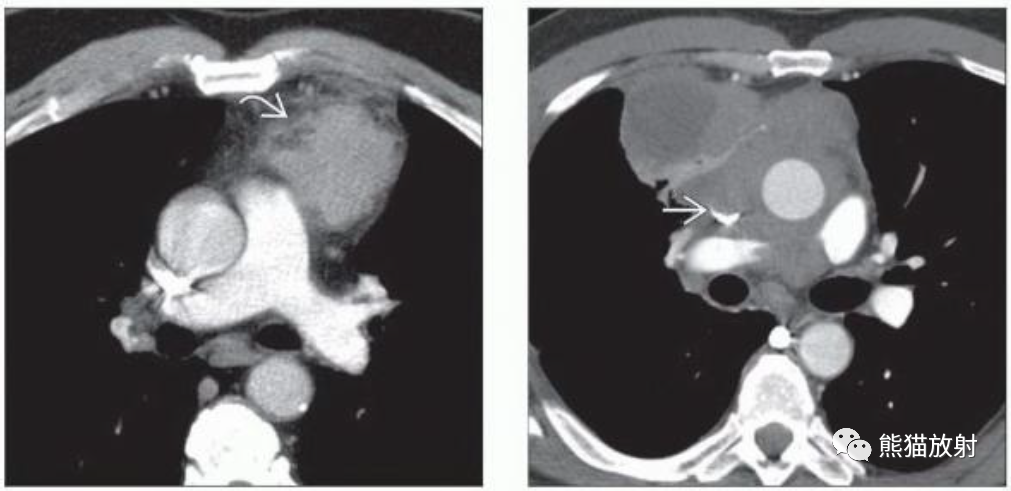

(左) 轴位ct显示左前纵隔胸腺瘤,边缘不规则,邻近纵隔脂肪浸润。手术中证实纵隔脂肪浸润 (IIa期) 。

(右) 侵袭性胸腺瘤。CT显示纵隔巨大分叶状肿块,包绕纵隔血管并侵犯上腔静脉。考虑到为III期疾病的影像学表现,患者应接受术前新辅助化疗。